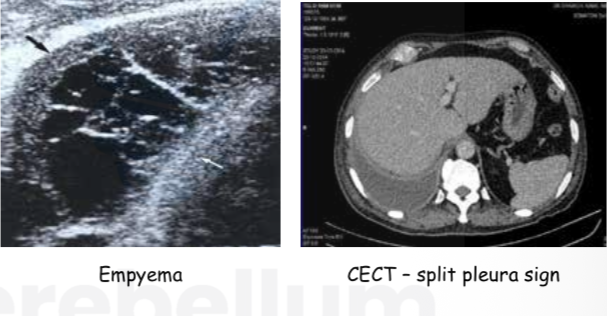

Radiological diagnosis of pleural effusion